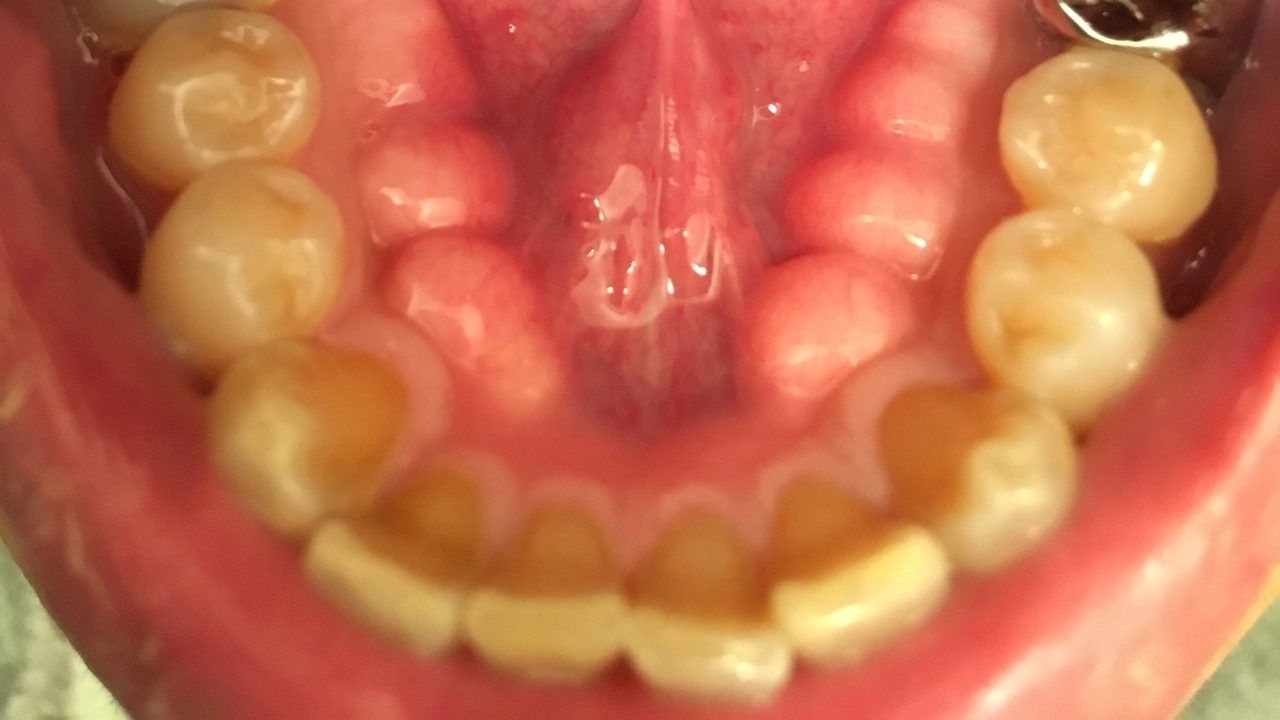

骨隆起が生じる

骨隆起(こつりゅうき)は、強い噛みしめや歯ぎしりなどにより力が過剰にかかることで、骨が発達する現象です。口蓋(上あごの部分)や下あごの舌側で骨が盛り上がります。

入れ歯を作る際などにこの骨が邪魔になり、削らなければいけないケースもあります。